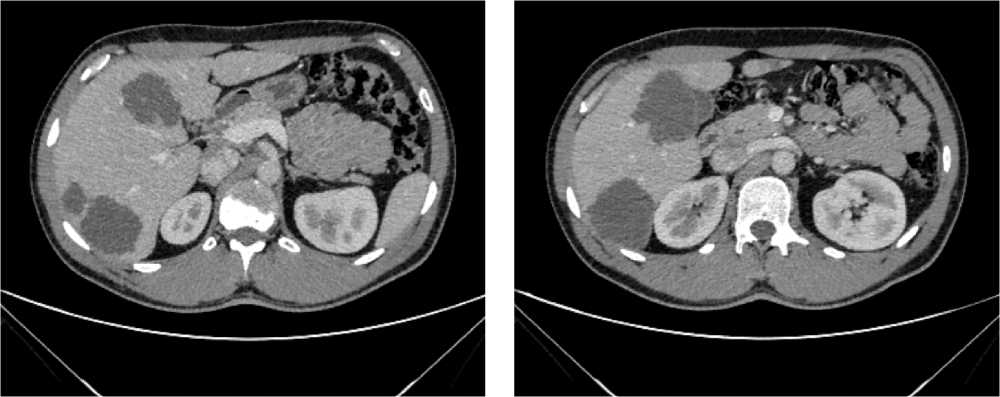

С июля 2022 г. у пациента отмечено появление эпизодов субфебрильной лихорадки. По результатам КТ органов брюшной полости от 08.2022 г. в проекции селезенки выявлена неоднородная инфильтрация с включениями, воздушной полостью в структуре, с тенденцией к отграничению и с распространением в параколическую клетчатку размерами 125 × 98 × 96 мм. Опухоль распространяется на большую кривизну желудка, вызывая утолщение стенки толщиной до 37 мм. По передней брюшной стенке справа отмечается округлое образование размерами 10 × 9 мм (рис. 5).

Рис. 5. Результаты компьютерной томографии органов брюшной полости у пациента 62 лет с диагнозом метастатический колоректальный рак с признаками микросателлитной нестабильности (август 2022 г., до лечения)

Fig. 5. Results of a CT scan of the abdomen of a 62-year-old patient with metastatic MSI-H colorectal cancer (August 2022, before treatment)

По результатам иммуногистохимического и молекулярно-генетического исследований, выявлены признаки dMMR/MSI-H (не экспрессируется MLH1) и мутация G12D в 12 кодоне гена KRAS.

По решению мультидисциплинарной комиссии, с учетом выявленного прогрессирования заболевания, его распространенности (массивный опухолевый конгломерат в левом подреберье, вовлекающий близлежащие петли кишки и дистальные отделы желудка, поджелудочную железу), ограничивающей проведение хирургического лечения, биологического статуса опухоли (dMMR/MSI-H), соматического статуса пациента ECOG-2 (обусловлен болевым синдромом), рекомендована 1 линия иммунотерапии пембролизумабом.

По результатам КТ органов брюшной полости (ОБП) от 08.2023, поддиафрагмально слева сохраняется инфильтрат 79 × 46 мм, распространяется на большую кривизну желудка, брюшину, диафрагму слева и по левому фланку брюшной полости. Желудок деформирован, стенки утолщены. Парагастральная и внутрибрюшинная клетчатка слева инфильтрирована. По брюшине сохраняются образования. Эффект лечения оценен как частичный регресс (рис. 6).

Рис. 6. Частичный регресс, по данным компьютерной томографии органов брюшной полости, на фоне иммунотерапии пембролизумабом у пациента 63 лет с диагнозом метастатический колоректальный рак с признаками микросателлитной нестабильности (август 2023 г.)

Fig. 6. Partial regression according to abdominal CT scan during immunotherapy with pembrolizumab in a 63-year-old patient with metastatic MSI-H colorectal cancer (August 2023)